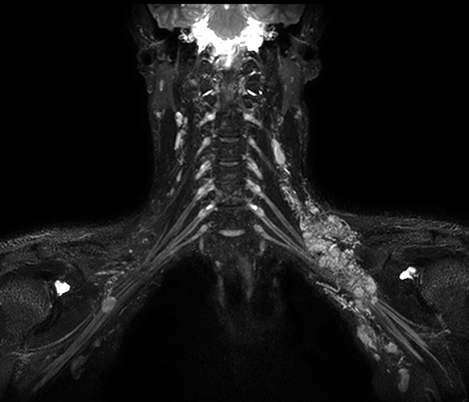

Casos clínicos de praticamente todas as anatomias Explore mais de 100 casos clínicos dos seus colegas do mundo inteiro, que demonstram como a tecnologia de RM digital da Philips fortalece os seus recursos de diagnóstico por imagem.